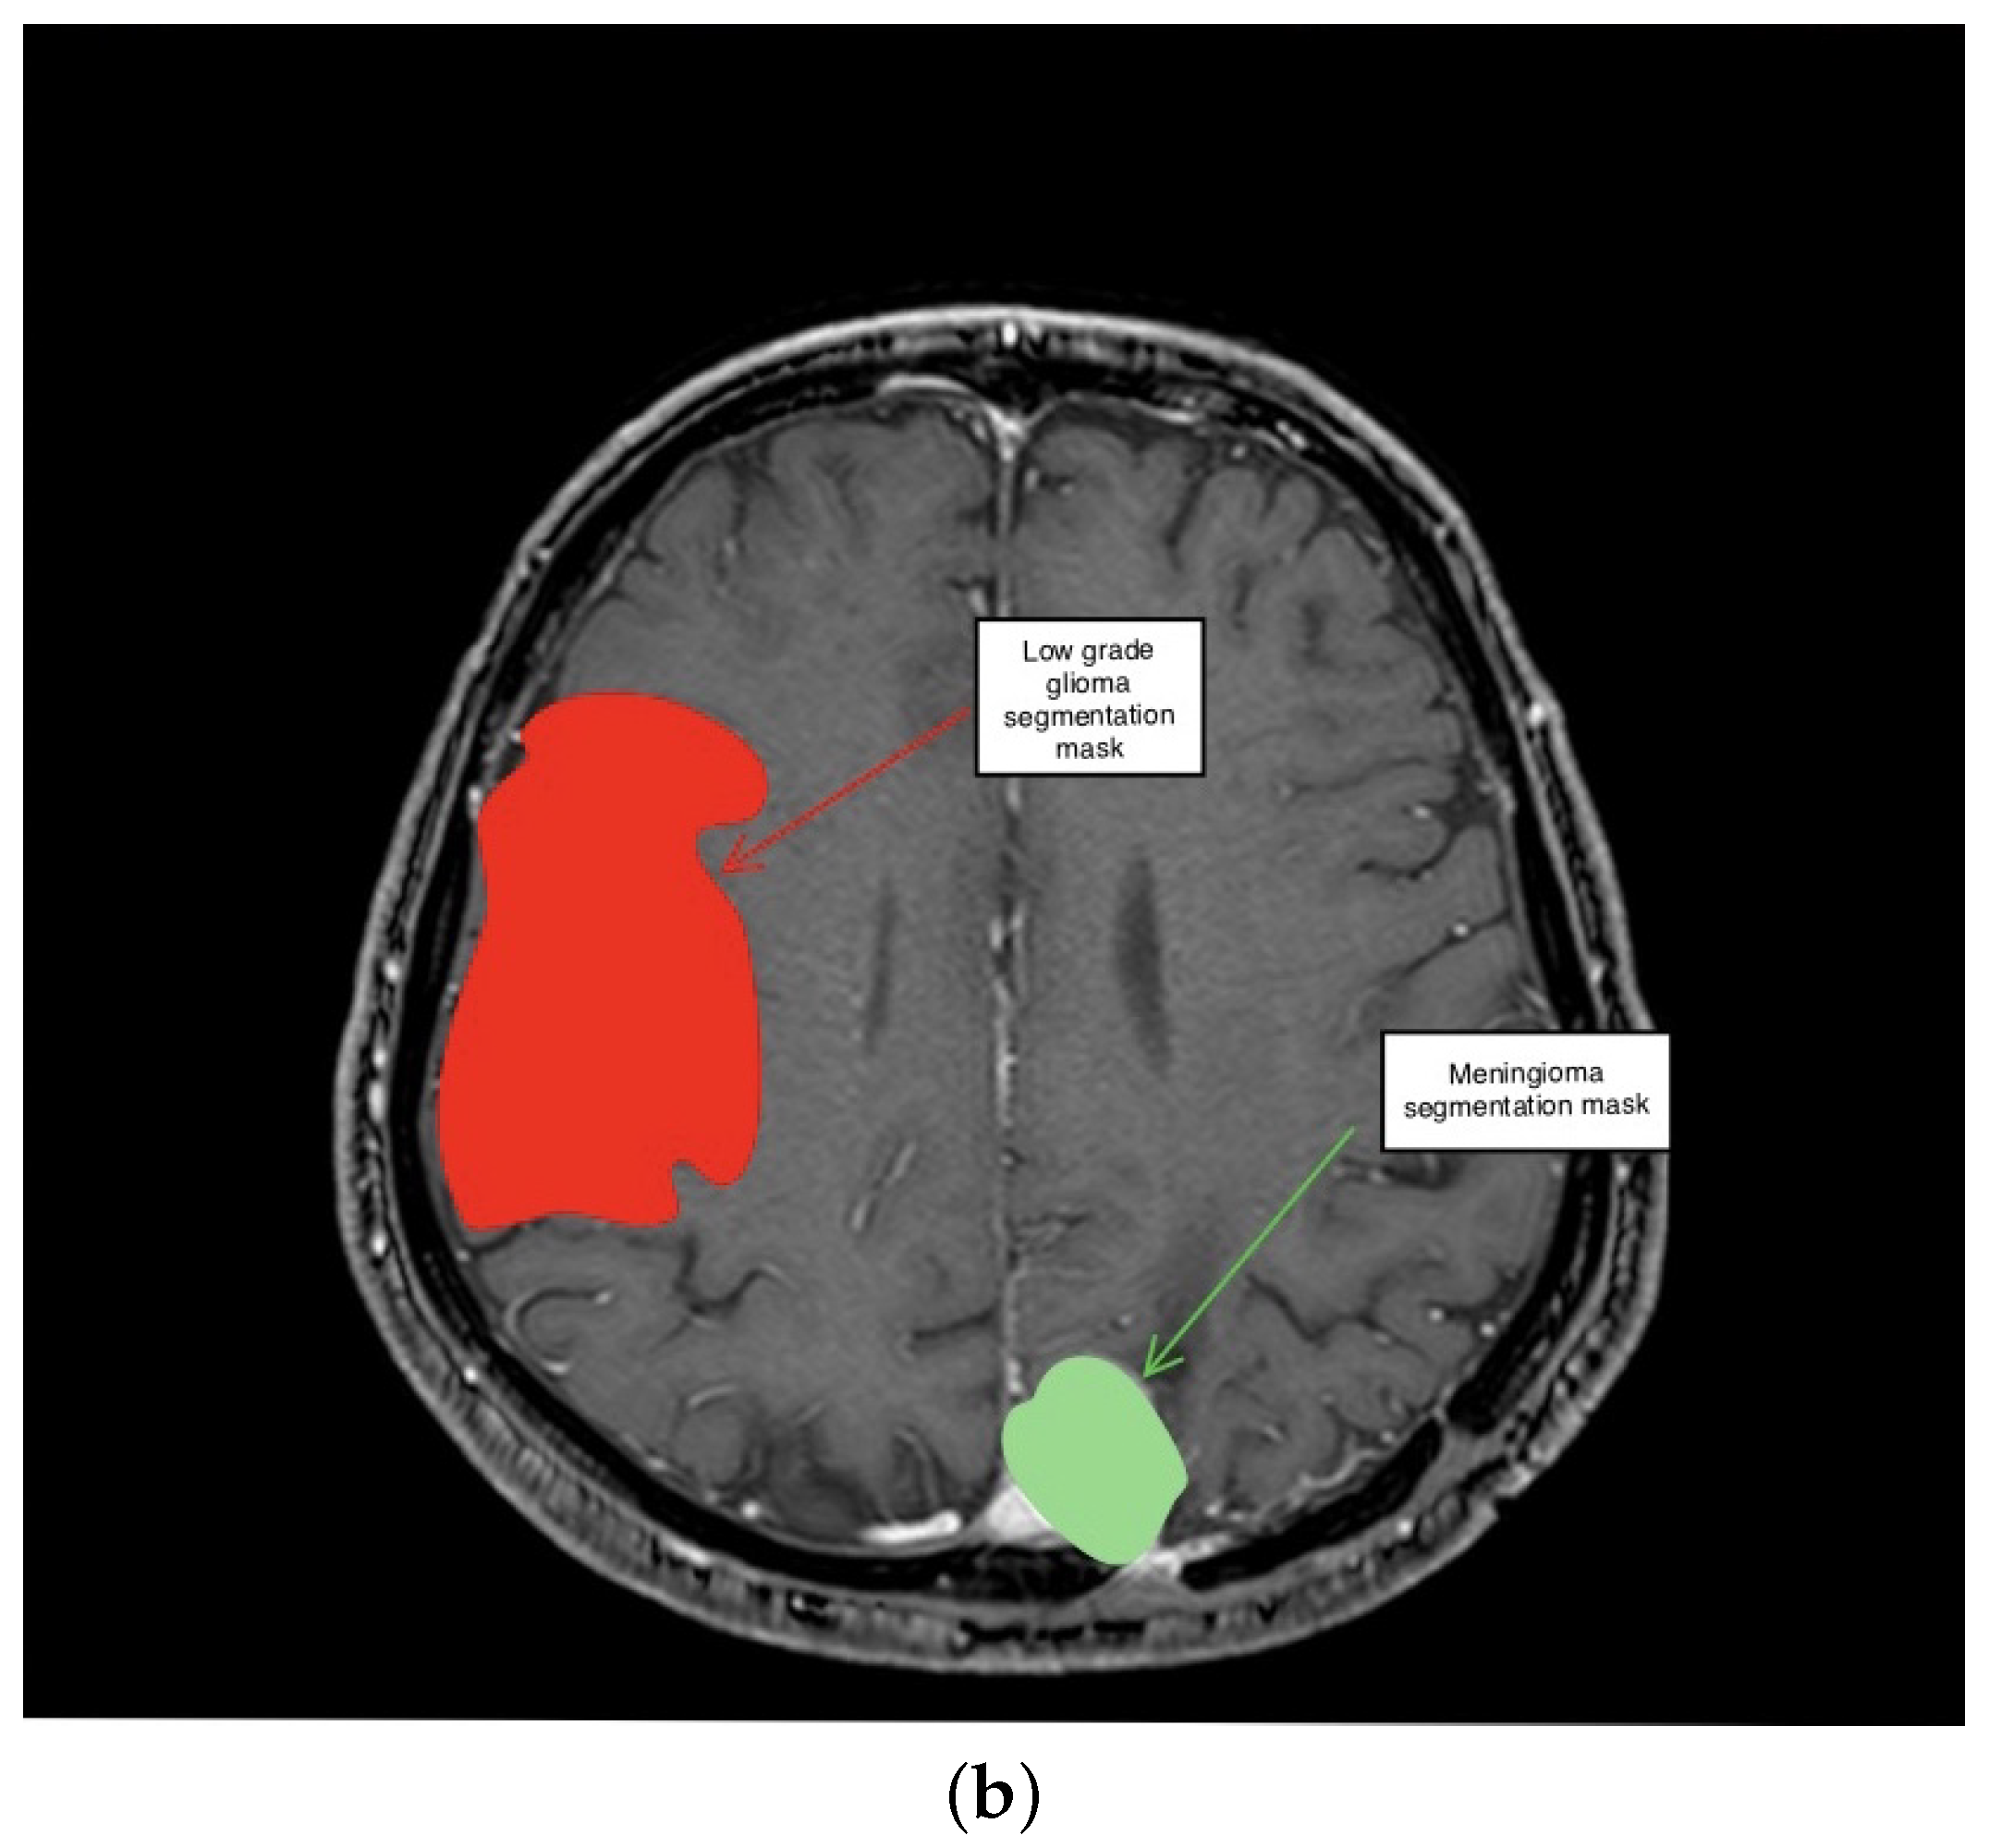

3.1. First Scenario

3.2. Second Scenario

3.3. Third Scenario